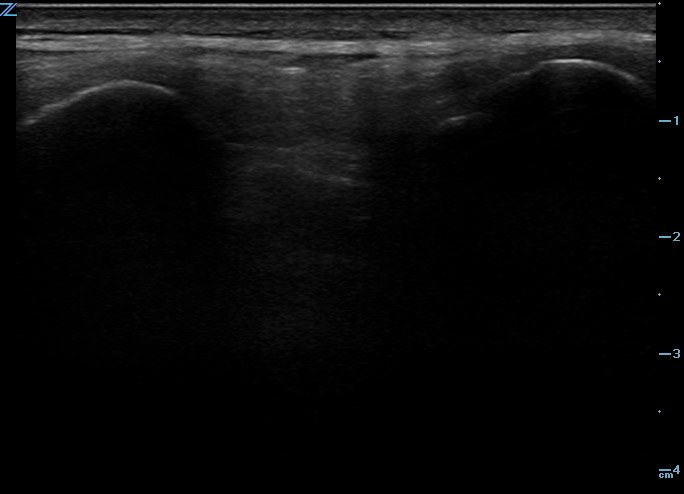

One recommended approach is to start with the probe in transverse position at the level of the sacrum and scan superiorly, sequentially identifying the spinous processes of L5, L4, L3, and L2. In the transverse orientation, spinous processes are seen as small, hyperechoic marks with dense vertical shadowing (Figure 1). With the probe centered over a spinous process, the operator uses a clean towel to wipe off excess gel, and a skin marker to place a vertical hash mark above and below the midline of the probe (Figure 2). Next, the probe is placed in longitudinal orientation over the same spinous processes, with the indicator toward the patient’s head. In this view, spinous processes will appear as wider, hyperechoic areas with distal shadowing (Figure 3). When two or more spinous processes are simultaneously visualized, the space between them is the area available for needle insertion. The skin is marked again, this time with horizontal hash marks extending outward from the midline of the probe (Figure 4).

Figure 3. Ultrasound image of spinous processes in longitudinal plane.